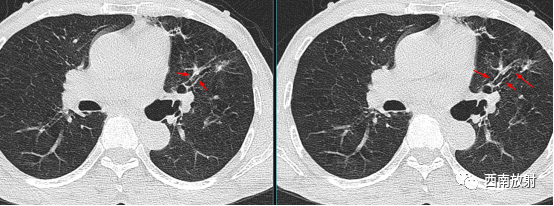

当扩大的支气管走行与扫描图像层面平行时,表现为轨道征。扫描层面有时与支气管不垂直或平行时,可以通过图像重建弥补。

▲图:右肺中叶炎症导致静脉曲张样支气管扩张,双轨征;

▲图:柱状支气管扩张,在扩张的支气管与扫描层面平行时,出现双轨征。